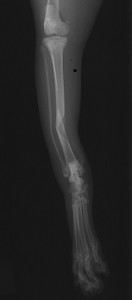

手術前 手術後

ロッキングプレートで整復しました。